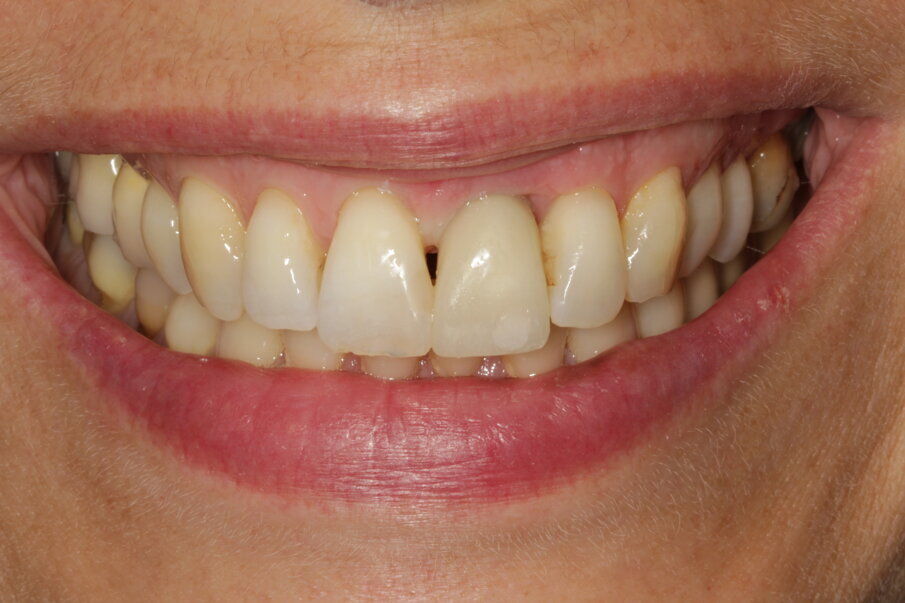

The female patient, aged 47 and a non-smoker, was in good general health. She performed regular oral hygiene and had good periodontal health. The patient experienced increasing mobility of the maxillary left central incisor and complained about compromised aesthetics due to the extrusion and progressive migration of the tooth in a buccal direction. The incisor had been treated with a crown at a preadolescent age after a violent trauma. The intraoral radiograph showed incomplete root development and evidence of a root canal therapy suggesting a strip perforation though no signs of periapical lesions were present. The shape of the crown was not symmetrical in relation to the triangular shape of the maxillary right central incisor, but had a wider and rectangular profile. Minor general gingival recession had led to the presence of a tiny inter-dental space. The marginal gingiva was reddened, and the central papilla was not symmetrical.

The photographic aesthetic evaluation showed that it would be very difficult to obtain symmetry in tooth shape and have good-looking and healthy soft tissue support at the same time. The patient’s maximum smile exposed the gingival contours. In such cases, it may be wise to consider also the possibility of altering the anatomy of the contralateral tooth with, for example, a ceramic veneer and discuss outcomes with the patient before finalising the treatment plan. This can be evaluated by performing the cut/copy/flip/paste sequence in reverse (Fig. 7). Together with the patient, it was decided to start performing the best possible replacement of the maxillary left central incisor and evaluate at an advanced stage with a temporary crown on the implant and mature, conditioned tissue whether to add a veneer to the maxillary right central incisor.